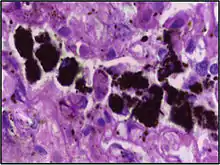

Alveolar macrophages are frequently seen to contain granules of exogenous material such as particulate carbon that they have picked up from respiratory surfaces. Such black granules may be especially common in smoker's lungs or long-term city dwellers.

Comparison of pigmented pulmonary macrophages

| Disease | Macrophage name | Macrophage pigment appearance (HE stain) | Usual macrophage location | Associated medical history | Image | Image comment |

|---|---|---|---|---|---|---|

| Anthracosis | Black-brown granules | Interstitium (perivascular) | ![]() |

Black arrow shows interstitial anthracotic pigment. Nearby macrophages (white arrow) can be presumed to contain anthracotic pigment. | ||